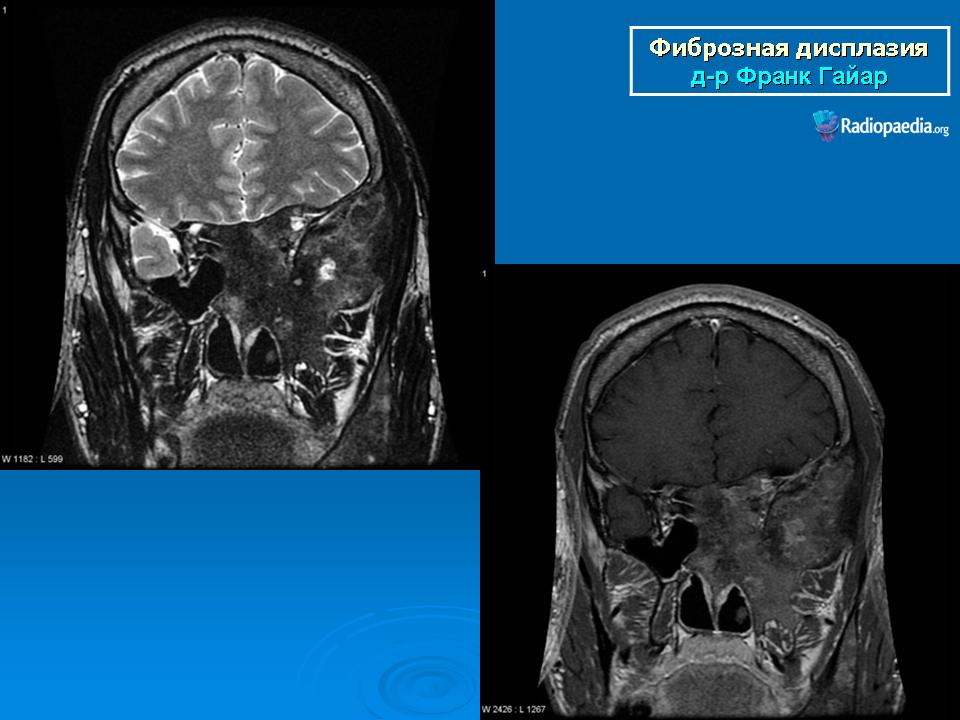

Фиброзная дисплазия

Для фиброзной остеодисплазии, или болезни Брайцева-Лихтенштейна, характерно нарушение костеобразующей функции мезенхимы, проявляющееся в одной или нескольких костях, что ведет к их деформации и образованию в них очагов разрежения, обычно отграниченных от здоровой ткани кости склеротической каймой. Объем пораженной кости при этом может быть увеличен. Чаще поражаются трубчатые кости, но характерные изменения могут отмечаться и в костях черепа. В таких случаях возможны облитерация придаточных полостей носа, деформация глазниц, сужение отверстий в основании мозгового черепа и в лицевом черепе, ведущее к нарушению функции проходящих через них нервов и сосудов. Заболевание, возможно, наследственное, проявляется с детских лет. Описал в I927 г. отечественный хирург В.Р. Брайцев (1878-1964), несколько позже - американский патологоанатом L. Lichtenstein (1906-1977).

Полиостотическая фиброзная дисплазия у пациента с синдромом Маккьюн - Олбрайта.